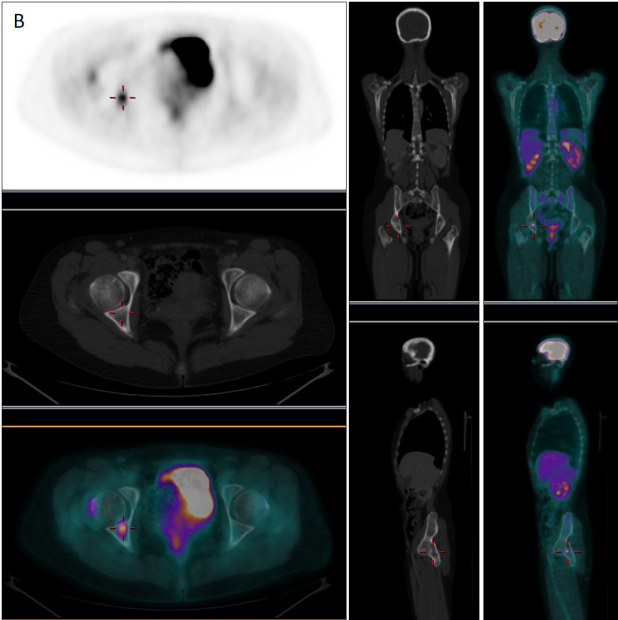

En febrero de 2019, ante la aparición de discreto dolor en cadera derecha y leve aumento del marcador tumoral CA-15-3 (35 U/mL) sospechosos de recaída, se realizó nueva GO que mostró persistencia de lesiones intensamente blásticas a predomino en columna vertebral, sin cambios respecto al estudio realizado 6 años antes (fig. 1-C). Se decidió realizar tomografia por emisión de positrones/TC con fluor-18-desoxi-D-glucosa (18F-FDG-PET/TC) para la caracterización de las lesiones invariables o detectar nuevas localizaciones sugerentes de recidiva. El estudio PET/TC (fig. 2B) demostró la presencia de una nueva lesión ósea intensamente hipermetabólica (SUVmax = 5,35) en región acetabular derecha, sin traducción aparente en la imagen radiológica, muy sugerente de recaída tumoral que justificaba la clínica y la reciente alteración analítica, mientras que el resto de las lesiones basalmente esclerosas e intensamente positivas en la GO resultaban completamente negativas desde el punto de vista metabólico (fig. 2A).

En el caso que presentamos, la GO permitió detectar correctamente diseminación ósea en el momento del diagnóstico, pero tras un adecuado manejo terapéutico, las lesiones esclerosas en TC continuaron exhibiendo durante años intensa actividad osteogénica, difícilmente interpretable en un contexto de remisión clínica y analítica. Sin embargo, ante una sospecha real de recaída tumoral, el estudio gammagráfico no demostró aparición de nuevas lesiones ni modificación de las previamente existentes. Por su parte, la PET permitió descartar viabilidad tumoral en las lesiones sospechosas en las técnicas de imagen convencional, permitiendo la detección de recaída ósea a través de una nueva lesión hipermetabólica que explicaba la aparición de signos analíticos y clínicos de recidiva.